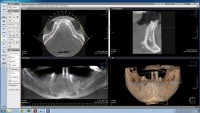

Computer tomograf 3D - CBCT

- CT 3D endo

- CT 3D partial

- CT 3D ATM

- CT 3D Mandibular

- CT 3D Maxilar

- CT 3D Total

- CT 3D Maxilar + sinus maxilar + ATM

- CT 3D Intreaga zona maxilo faciala 13X14,5cm

- CT 3D ORL